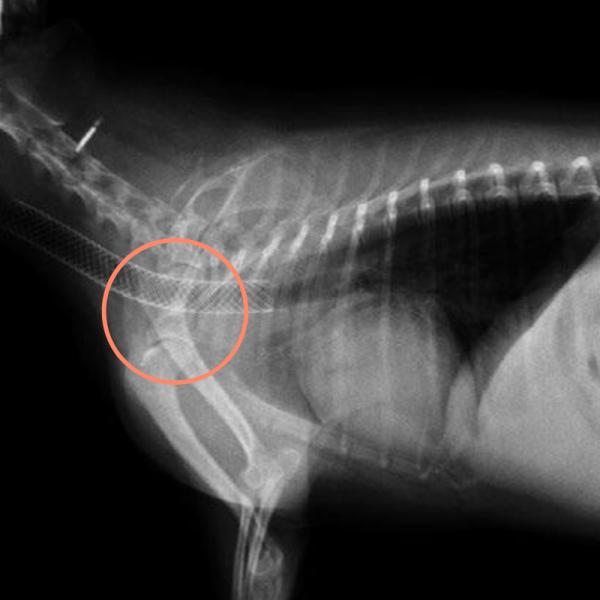

El colapso traqueal es una enfermedad que consiste en la compresión de la tráquea, el conducto que lleva aire desde la nariz hasta los pulmones. En consecuencia, la tráquea se estrecha y el gato no puede respirar.

El tratamiento del colapso traqueal en gatos dependerá de las causas que lo han provocado. En caso de que la causa sea un tumor, se recurrirá a la cirugía para poder extirpar el tumor. Si la causa es una obstrucción en la tráquea, se puede intentar retirarlas con una endoscopia.